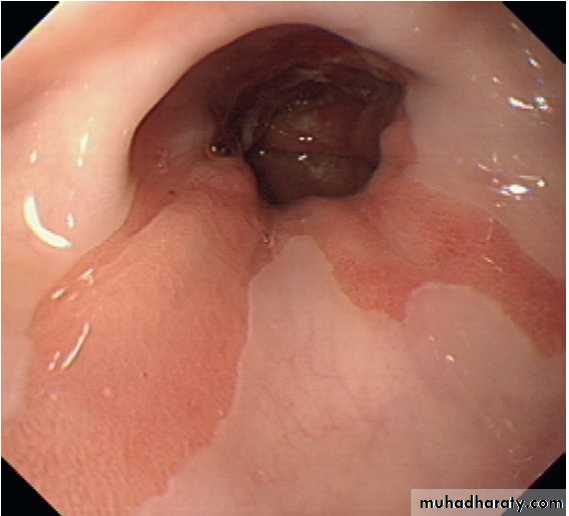

Barrett’s oesophagus.

Tongues of pink columnar mucosa are seen extending upwards above the oesophago-gastric junction.Treatment of gastro- oesophageal reflux disease: